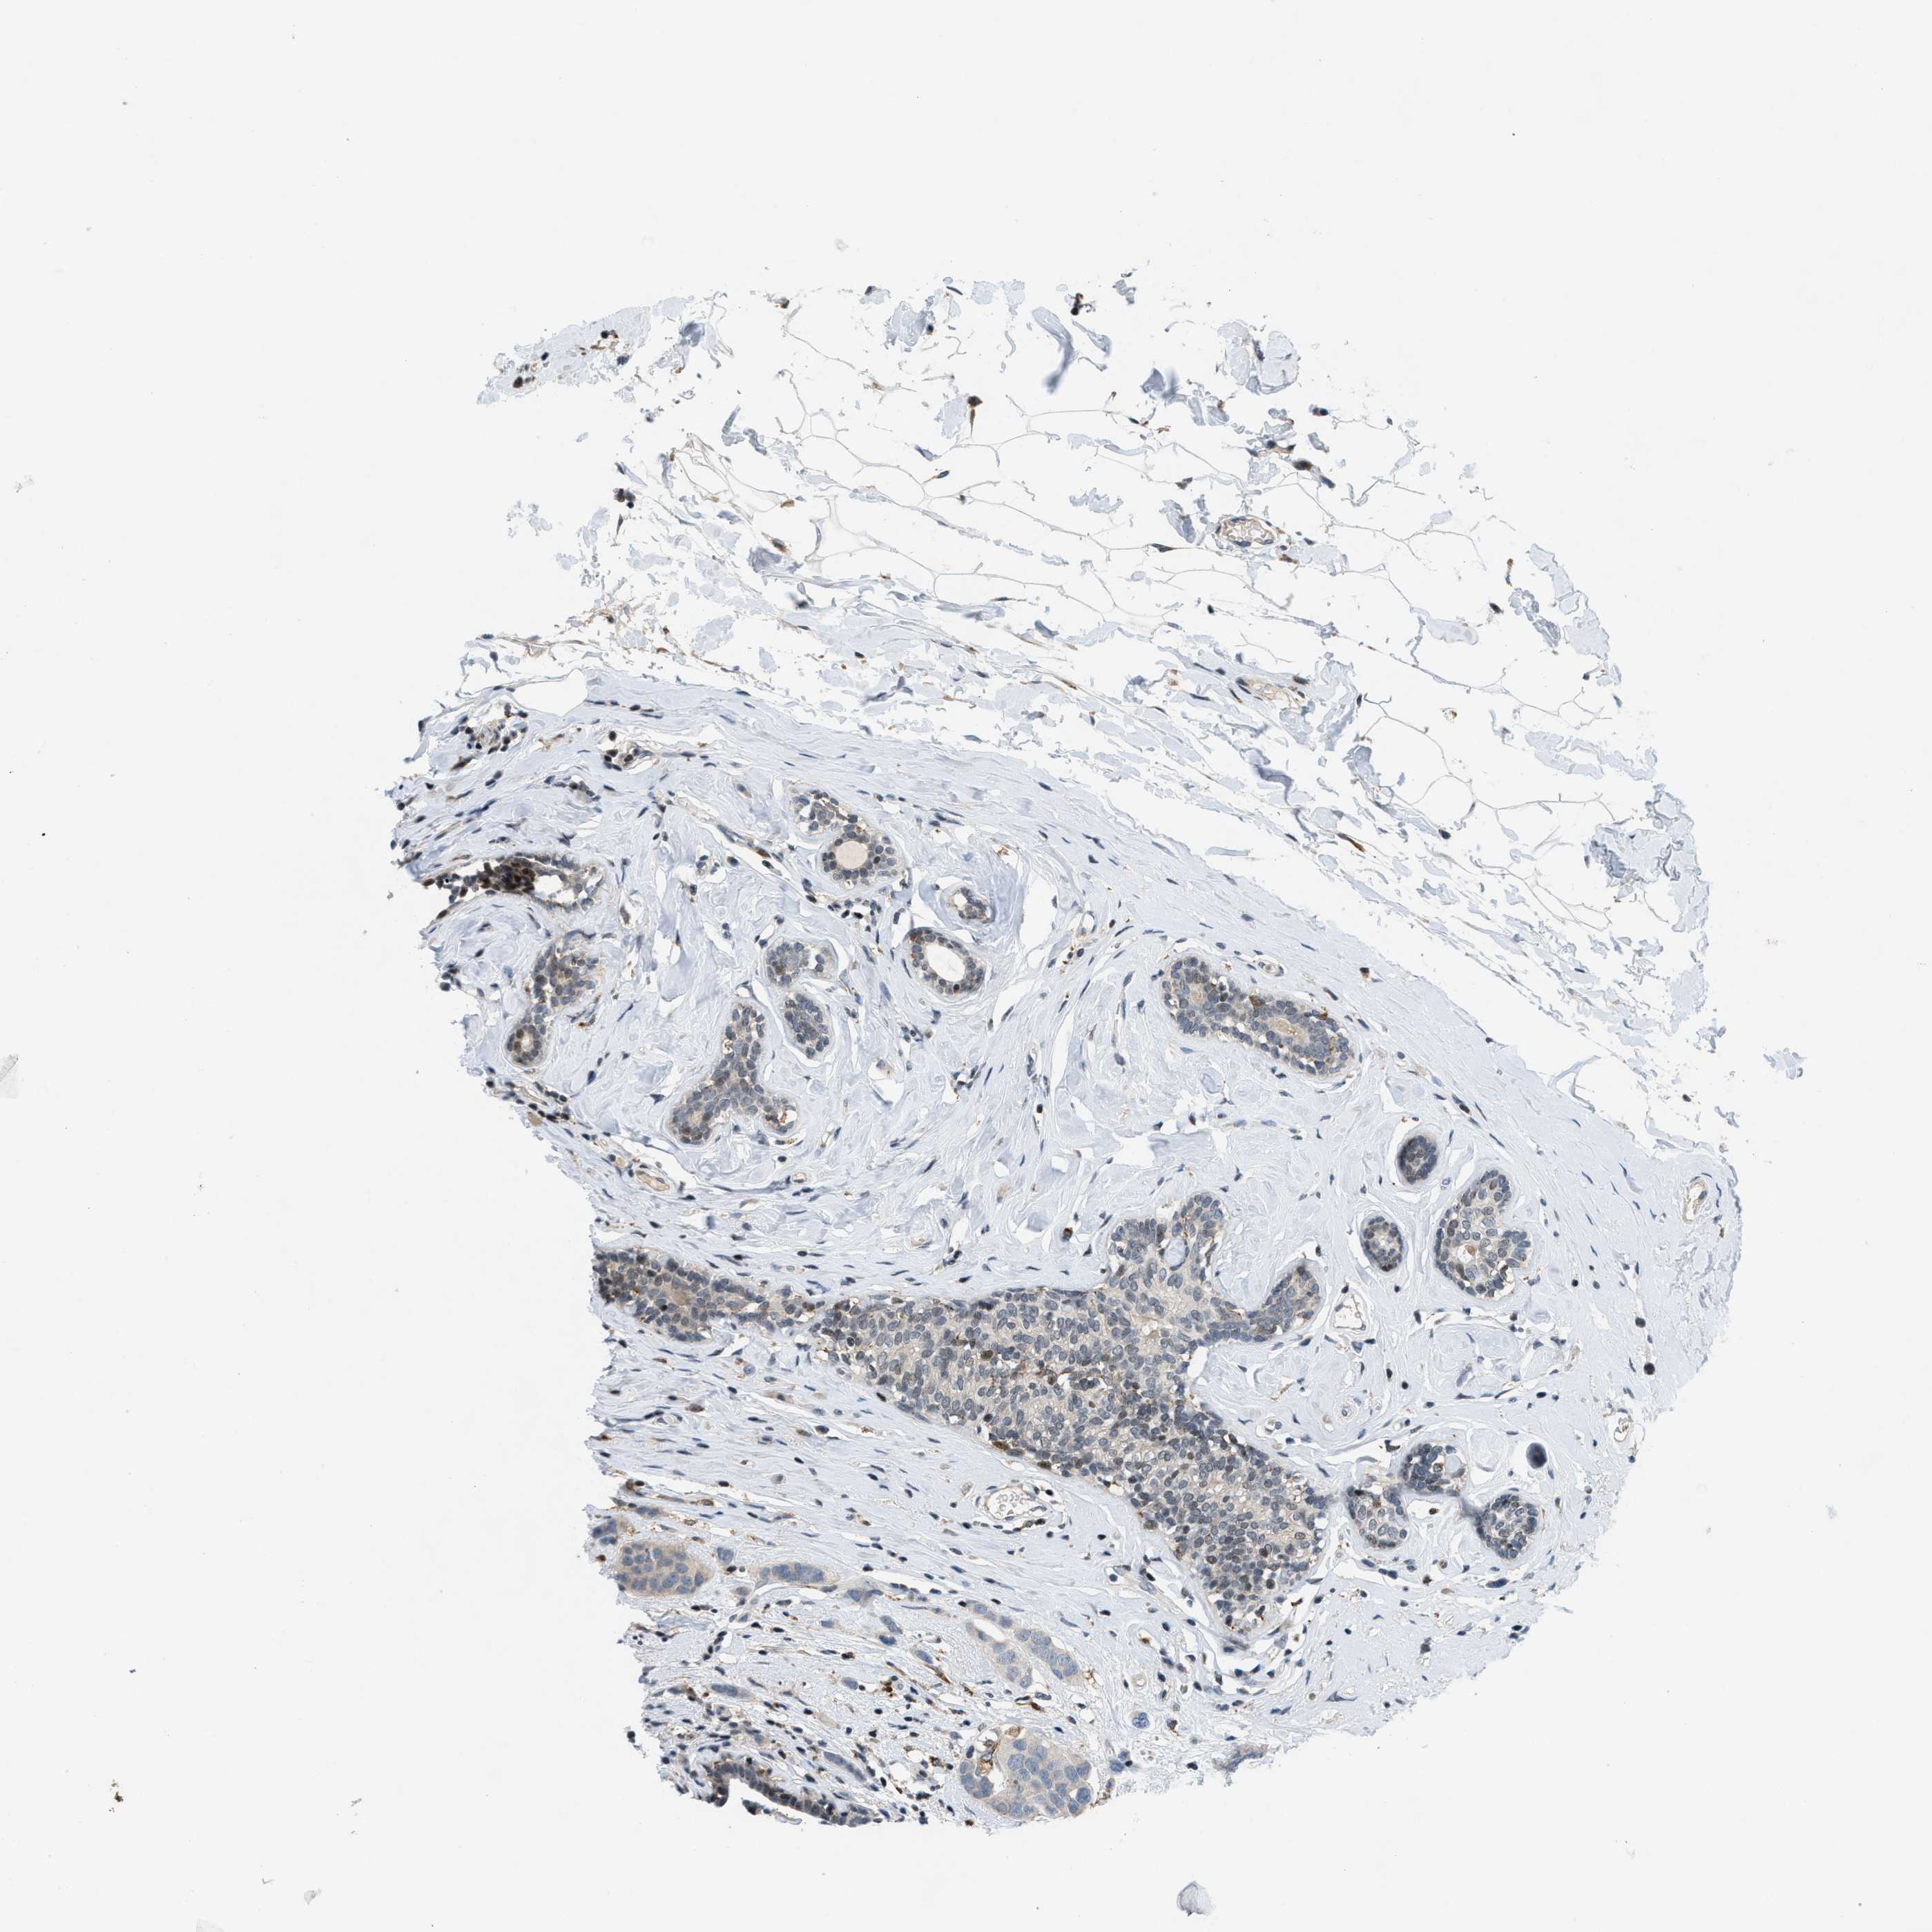

CANCER BREAST CANCER Show tissue menu

BRCA TCGA BRCA VALIDATION PROTEIN EXPRESSION

ANTIBODIES

AND

VALIDATION